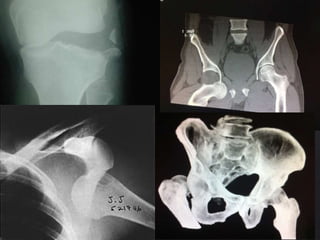

Luxación de Cadera

• Luxación posterior en la más

frecuente (85-90%)

• Lesión del N. Ciático en el

10-20% de las Luxaciones

posteriores.

Luxación de Rodilla

• Debe lesionarse al menos 3

de las 4 estructuras

ligamentosas de la rodilla.

– Lig. Cruzado anterior

– Lig. Cruzado posterior

– Lig. Colateral medial.

– Lig. Colateral lateral.